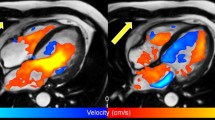

One of the unique advantages of 4D Flow is that en bloc flow velocity data can be acquired three-dimensionally with cardiac phase-resolved fashion, which means retrospective flowmetry is allowed for any vessels within the field of view. Unlike other modality like Doppler ultrasonography, the blood flow velocities of any vessels can be measured with arbitrary measurement sections even after patients left MR suite. This function is very convenient when multiple measurement points are required in one examination. The merit of this function is maximized in measuring the flow of each arterial branch of the transplanted kidney [5] or flow analysis for possibly responsible arteries for type II endoleak after endovascular repair (EVAR) for the abdominal aortic aneurysm [6, 7]. An attempt to measure the flow velocity and flow rate of certain blood vessels using the MR technique started 30 years ago, which had been an initial boom of MR flowmetry. For example, ischemia of the superior mesenteric artery (SMA) is a clinically interesting theme to be assessed by PC [8]. Dozens of researches have been performed using 2D cine PC since then [9,10,11,12,13,14,15,16]. Among these studies, some researchers noticed the fluctuations in the measured flow velocity [17], but the discussion has not been sufficiently done on the reason why the fluctuations of the blood flow velocities occur. The flow velocity in the lumen is not necessarily laminar. Instead, there are many abnormal flows such as eddy, vortex and helical in the winded vessels or the pathological vessels. Taking one representative case, for example, Ishikawa et al. [18] had observed the improved flow in the renal artery after the percutaneous transluminal renal angioplasty (PTRA). The stenosed segment in the left renal artery was balloon-dilated for a patient suffering from renovascular hypertension, and then, her systemic blood pressure was normalized immediately. 4D Flow and CFD (computational fluid dynamics) were performed before and after the dilatation. The time velocity patterns measured at the similar measurement planes before and after the intervention was different. Although the area under the curve increased after PTRA, the complexity of the streamlines in the flow path as well as the fluctuated time-velocity curve puzzled them. Before PTRA, vortex flow within the post-stenotic dilatation was dominant and fluctuation occurs in the measured values (Fig. 9b). With a close look at the streamline; however, it was easy to understand that the vortices in the post-dilated segment of the renal artery were responsible for this fluctuation. This phenomenon was also reproduced by the CFD simulations as well (Fig. 9). Also in flowmetry for healthy vessels, this problematic non-laminar flow should be kept in mind. Take superior mesenteric artery (SMA) for instance, physiological helical flow may be dominating at the curved portion (Fig. 10) [19]. Therefore, when we measure the flow velocity and flow rate of specific vessels, we first perform streamline analysis with 4D Flow and then determine the measurement planes that can avoid abnormal flow. These flowmetry issues associated with complexed flow dynamics have not been fully discussed previously, probably because there has been no imaging technology to directly visualize the flow dynamics. Using these capabilities, 4D Flow is becoming an essential tool for qualitative and quantitative flowmetry for the vessels with complexed flow (Figs. 11, 12). For instance, Suwa et al. [20] found a fairly large whirlpool in the left atrium and the ventricle (Fig. 10) of the healthy volunteers, which was observed more often in individuals with normal cardiac function rather than degraded cardiac function [21].